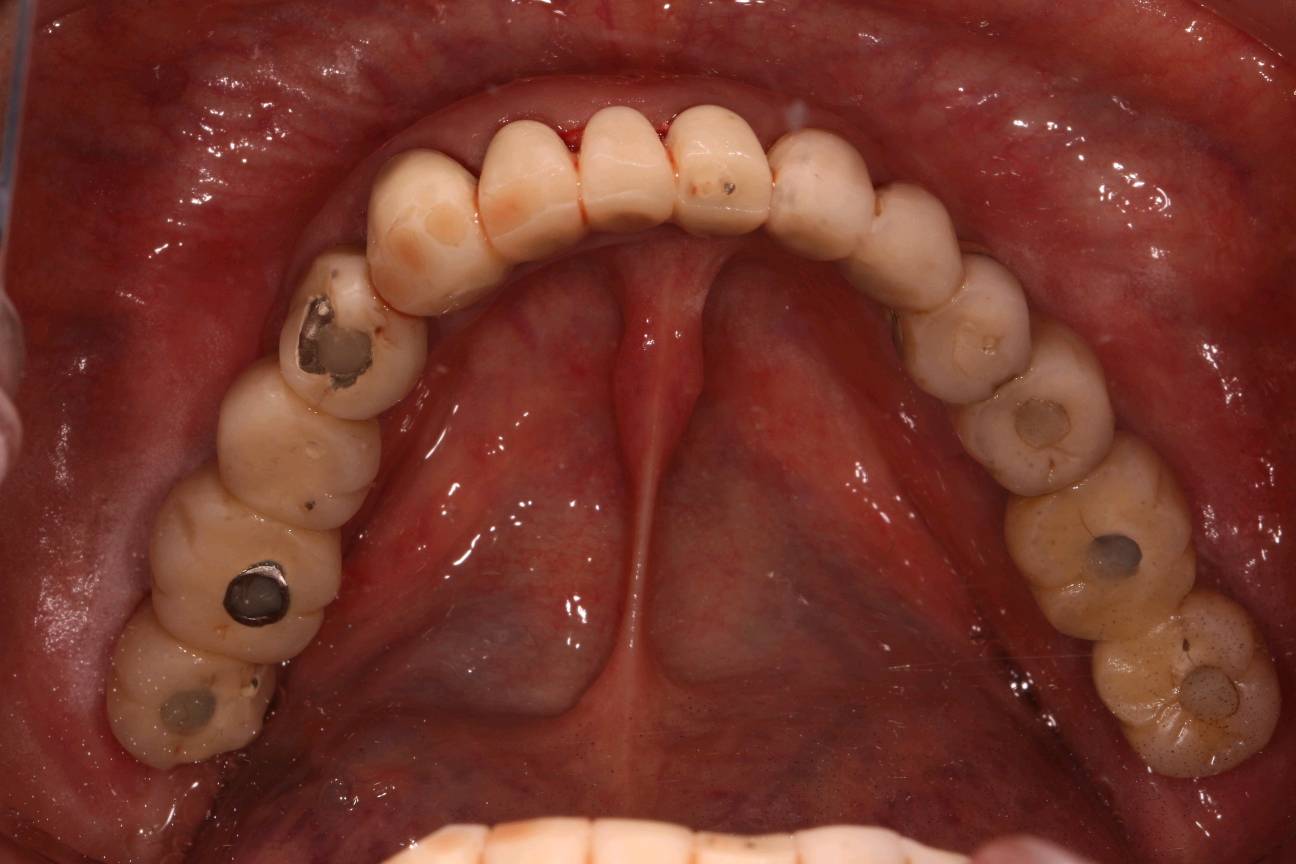

程先生,80岁种植牙复诊,共种了17颗牙,距离第一颗种植牙己定期随访15年,无松动疼痛等症状,用的很是满意。

本次复诊进行了OHI口腔卫生宣教,刷牙、牙线、间隙刷使用宣教和全口超声波洁治,喷砂洁治,抛光,上药,并愉快的约了明年今日复诊。